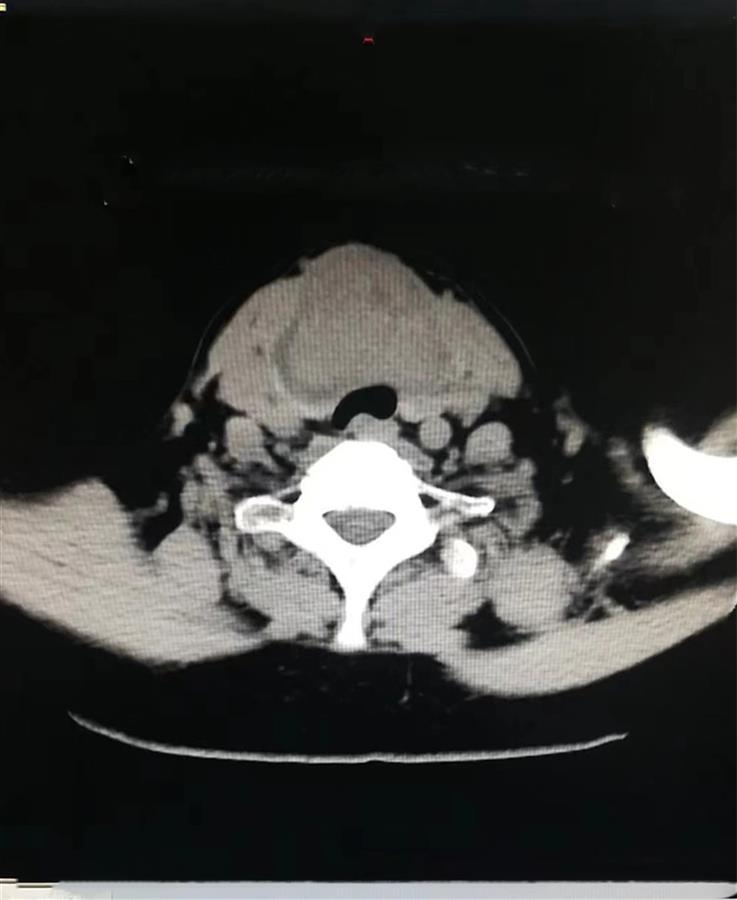

病人颈前包块压迫气管

甲乳外科团队进行了认真的术前讨论,制定了周密的手术方案,于2023年3月11日上午在全身麻醉下为患者行甲状腺根治性切除+双侧颈区功能性淋巴结清扫术,术中见双侧甲状腺肿瘤融合成团,位于气管前方,大小约6cm,手术经过顺利,出血少。术后,通过病理切片,提示甲状腺B细胞性非霍奇金淋巴瘤。